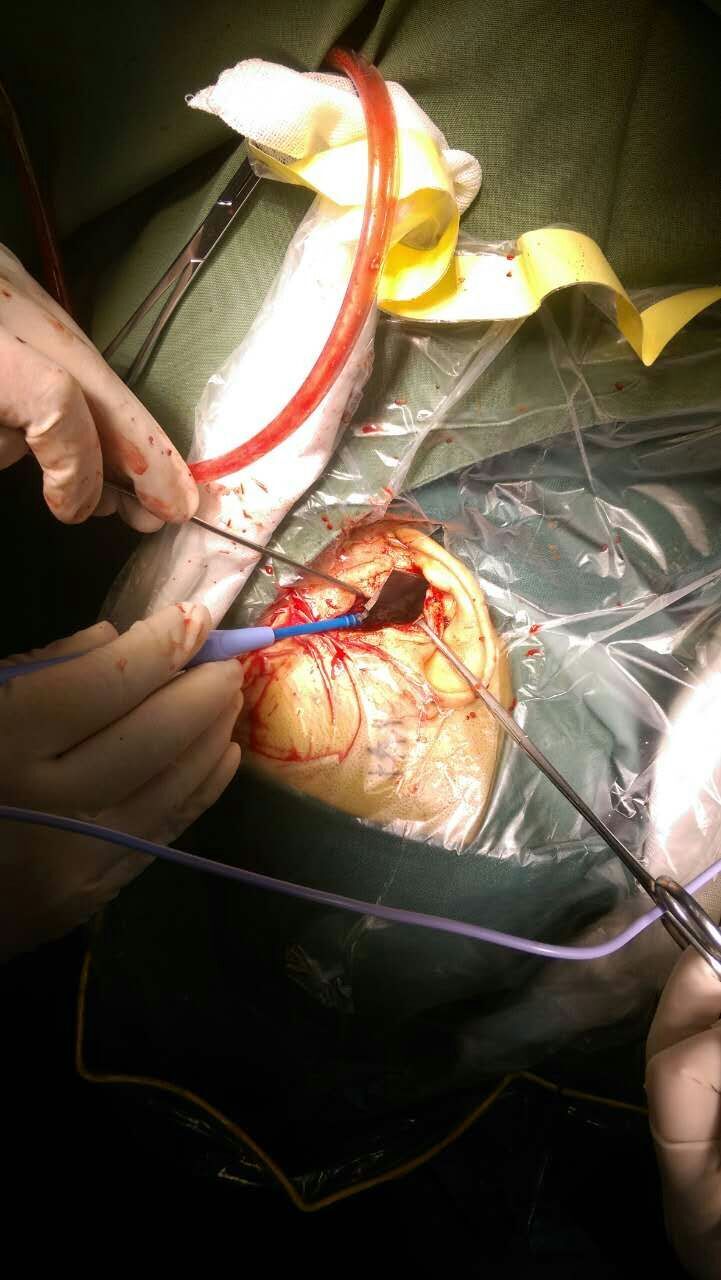

危急关头,神经外科、急诊科相互配合,迅速做好术前准备,以最快的速度将夫妻二人送入手术室。王冰主任带领专业团队,在麻醉科的配合下先后对夫妇二人进行了“开放性颅脑损伤清创术、异物取出术、颅骨整复术、耳廓成形术及颌面部多发裂伤清创缝合术”和“开放性颅脑损伤清创术+凹陷骨折整复术+硬膜外血肿清除术”。术中发现残留在丈夫颅内的刀具十分贴近大血管(图3),稍不留意就会引起颅内大出血,造成病人死亡。王冰主任凭借多年的临床经验及娴熟的手术技巧,经过3个多小时的努力,终于将残留在丈夫颅内的刀具完整取出(图4)。术后夫妇二人神志清楚,恢复良好。现已由监护室转入普通病房继续治疗。

图3 (术中见刀具残端)

图4 (完整取出的刀具)